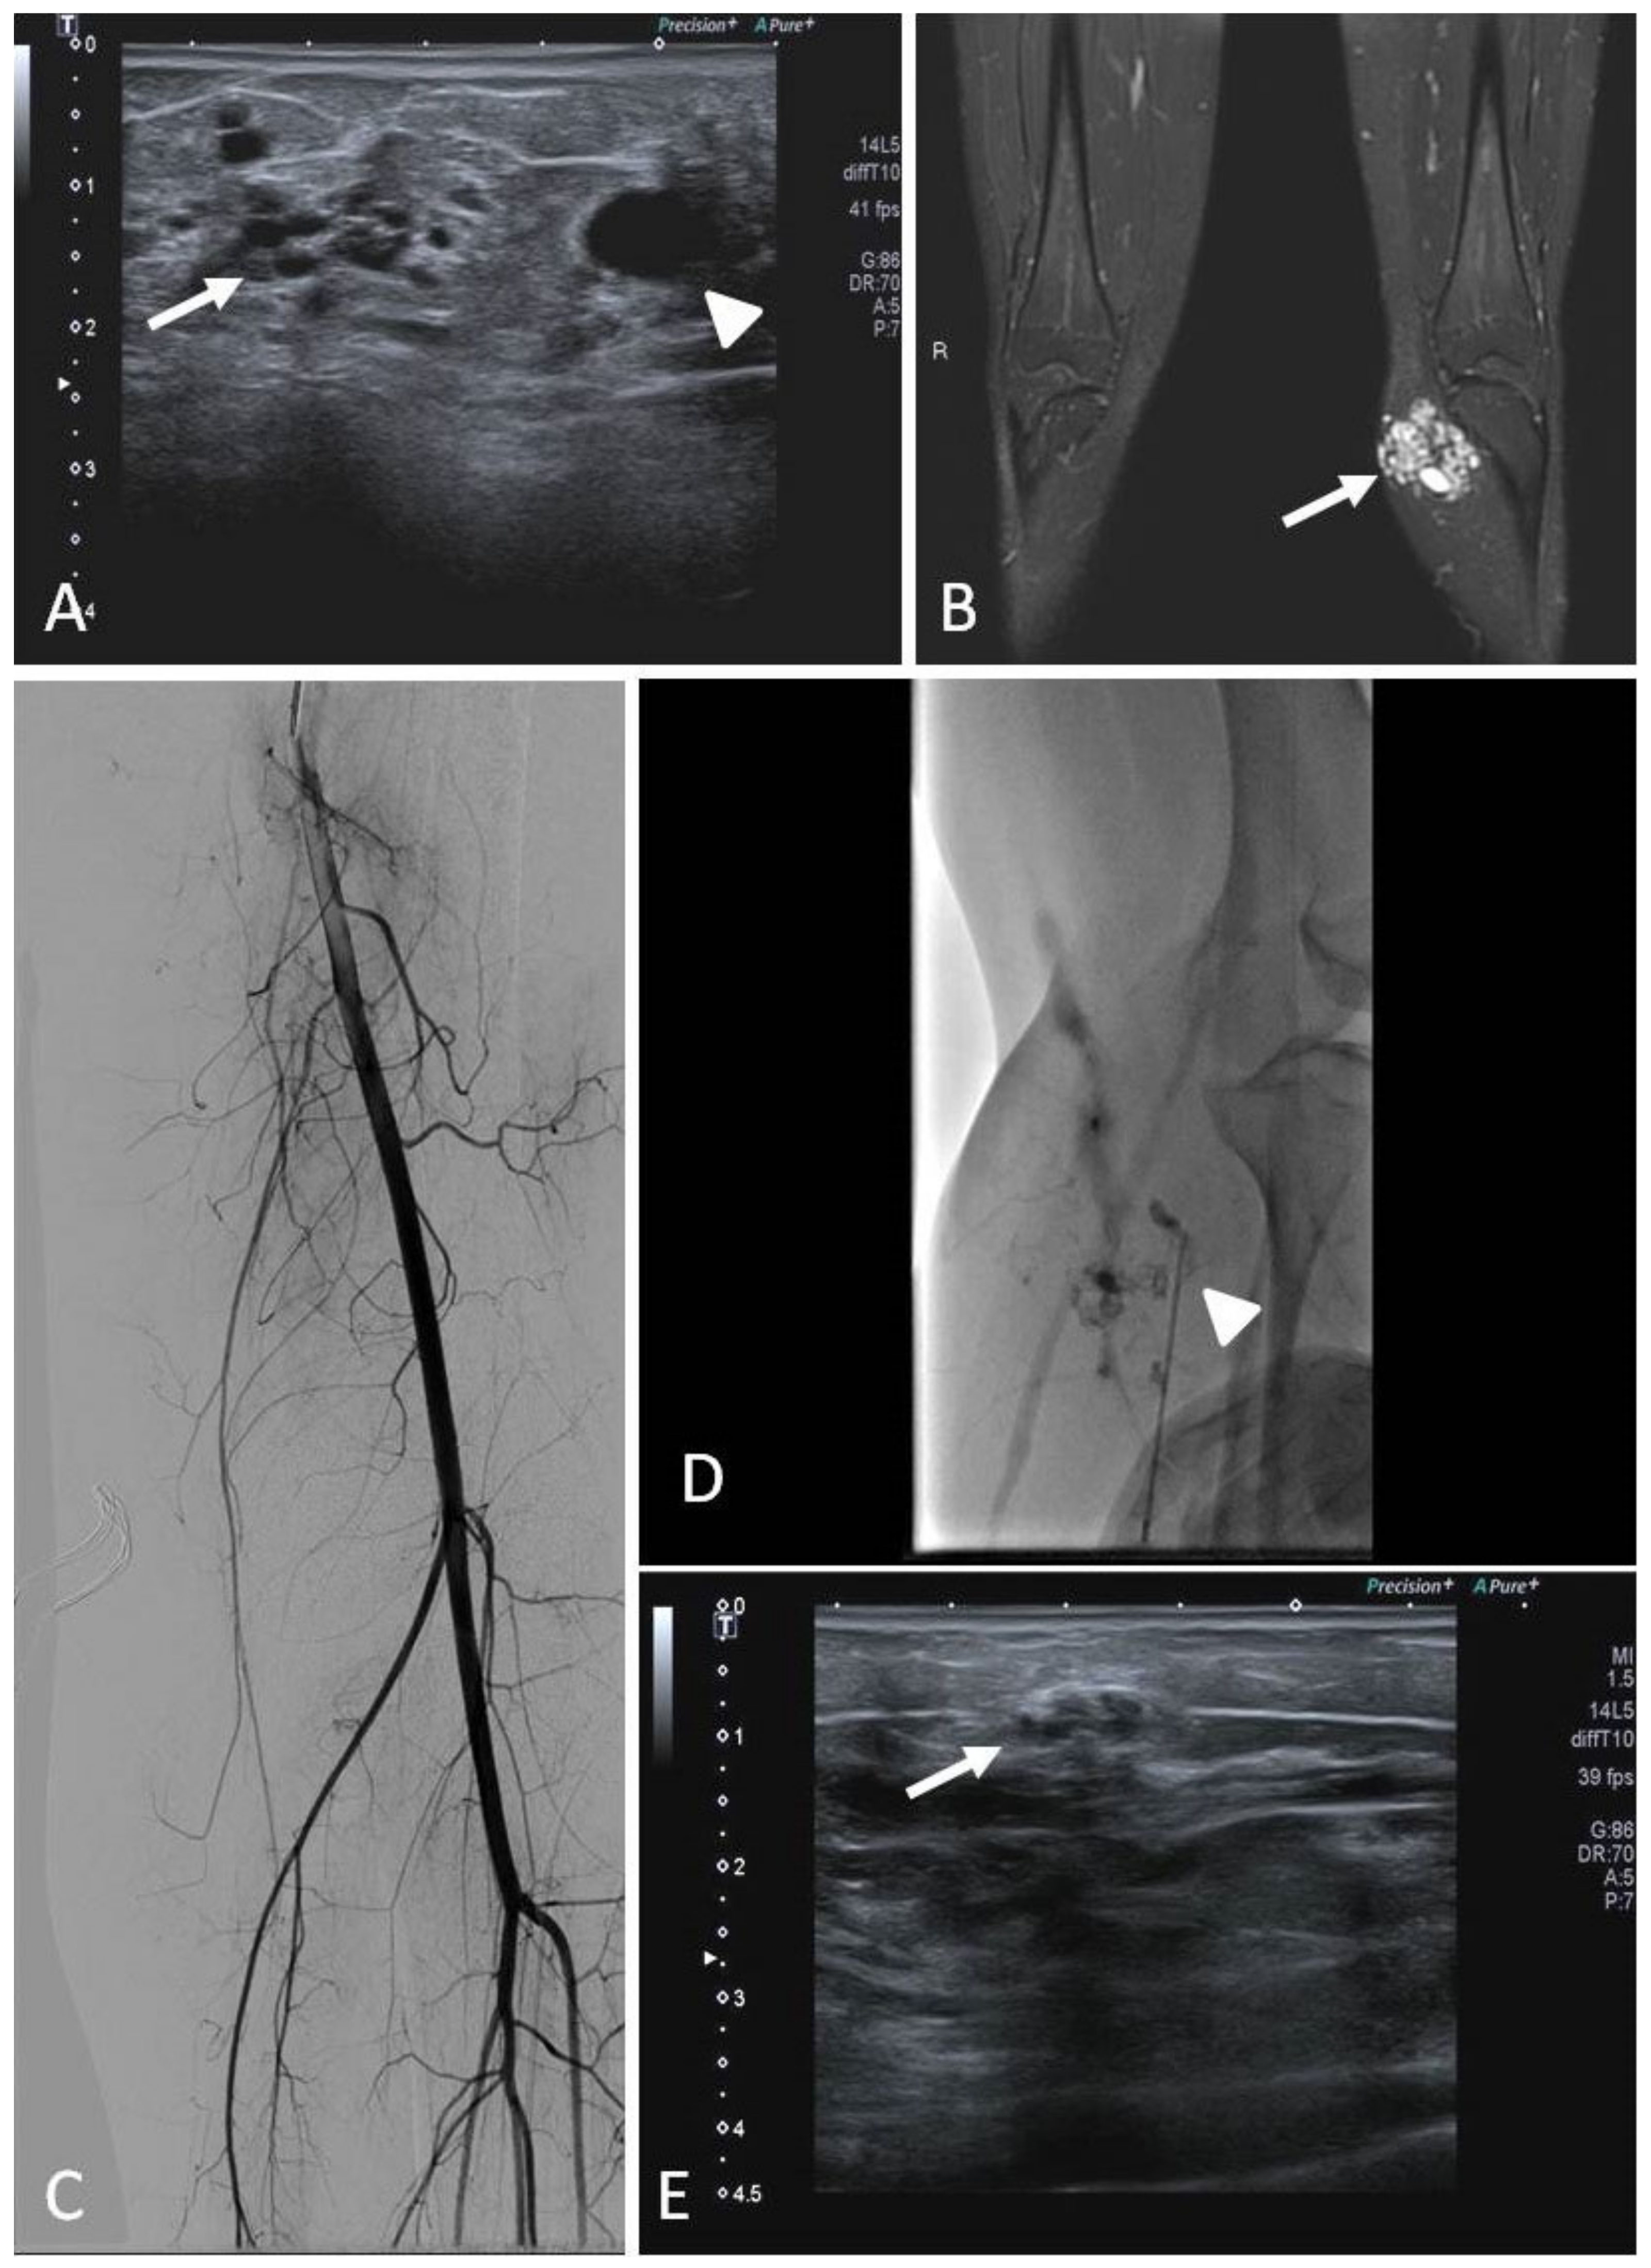

7. Congenital and Acquired Vascular Malformations (VMs)

7.1. Indications

7.2. Techniques

7.3. Clinical Outcomes